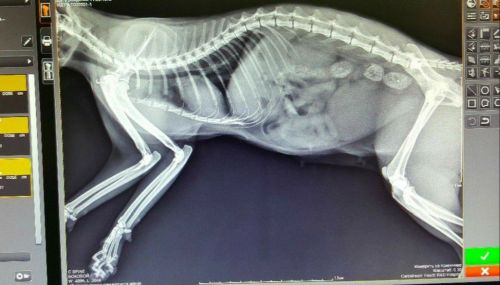

На вооружении наших врачей лабораторная диагностика, УЗИ - диагностика,  и прочее современное специализированное оборудование.